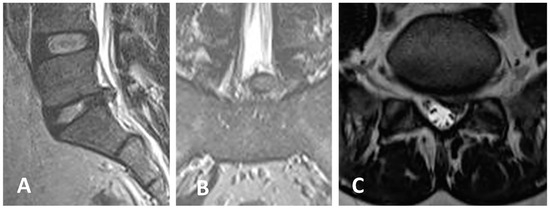

3.3. Clinical Case 1